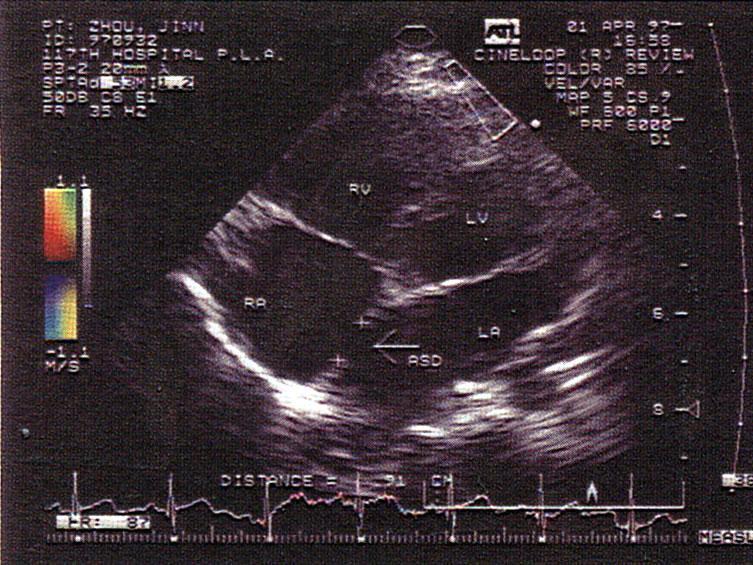

以上房间隔缺损属于哪型?(?)A.原发孔型B.继发孔型C.上腔型D.下腔型E.混合型

问题 以上房间隔缺损属于哪型?(?)

选项 A.原发孔型 B.继发孔型 C.上腔型 D.下腔型 E.混合型

答案 B